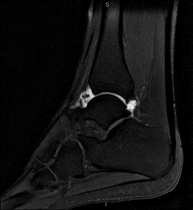

- Ankle MRI arthrography

Examination to study injuries to small anatomical structures of the joint that are commonly injured in patients suffering from dislocation or chronic instability. Prior to the examination, a contrast fluid is injected into the joint, guided by X-ray imaging. The total duration of the two procedures is 50 minutes.